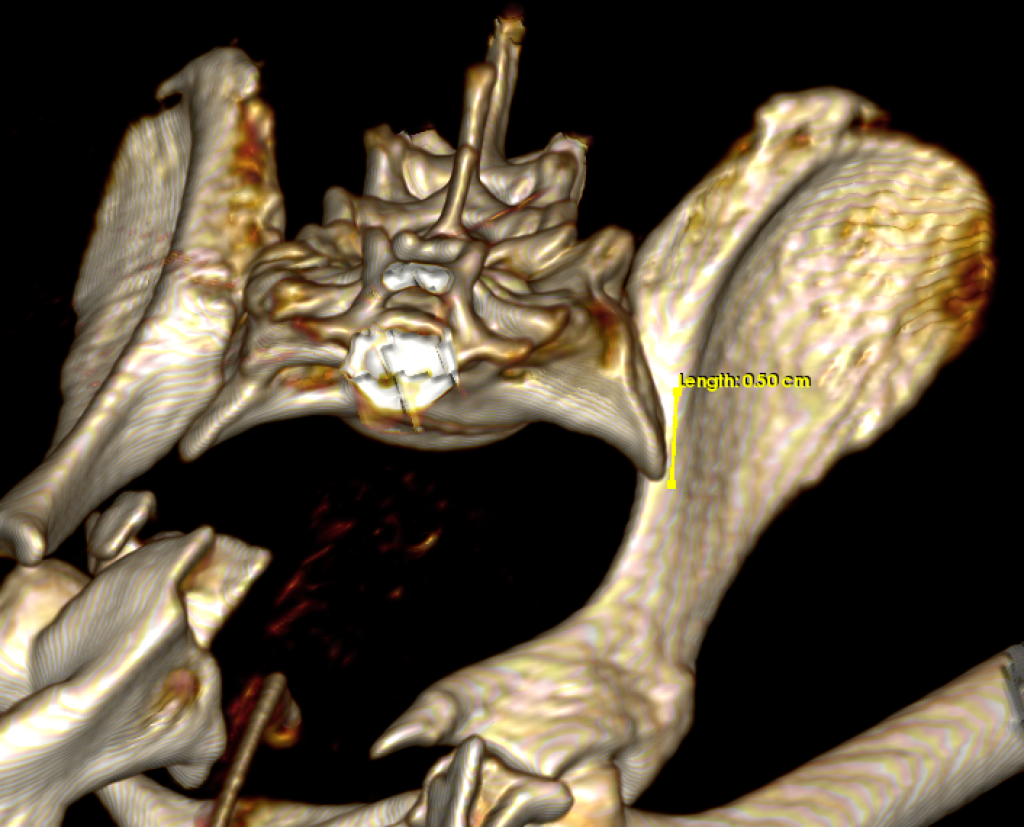

Para obtener un diagnóstico definido, procedimos a realizar un protocolo diagnóstico completo, que incluyó un estudio radiológico y tomográfico de la pelvis. Gracias a las imágenes pudimos confirmar el diagnóstico, una fractura múltiple de pelvis con luxación sacroiliaca derecha, y luxación coxofemoral izquierda a consecuencia de una fractura conminuta del acetábulo.

Para poder definir con mas precisión todos los daños y establecer el mejor plan quirúrgico realizamos una tomografía computarizada (TAC) de la pelvis.

La estabilización quirúrgica de la pelvis no resultó sencilla. En primer lugar se realizó un abordaje lateral al ilion y acetábulo izquierdo, a través de una osteotomía de trocánter mayor. Al comprobar la imposibilidad de reducción de los fragmentos que comprometían el acetábulo, se tomó la determinación de realizar una exéresis de la cabeza y cuello femoral. A continuación se estabilizó la fractura de la hemipelvis izquierda mediante una placa de bloqueo y titanio de 1´5 mm. La osteotomía del trocánter mayor se redujo y estabilizó por su lado con una banda de tensión.

En segundo lugar se realizó un abordaje dorsal a la articulación sacroiliaca derecha, que se encontraba luxada. Se redujo y estabilizó con dos tornillos para garantizar la fijación adecuada.